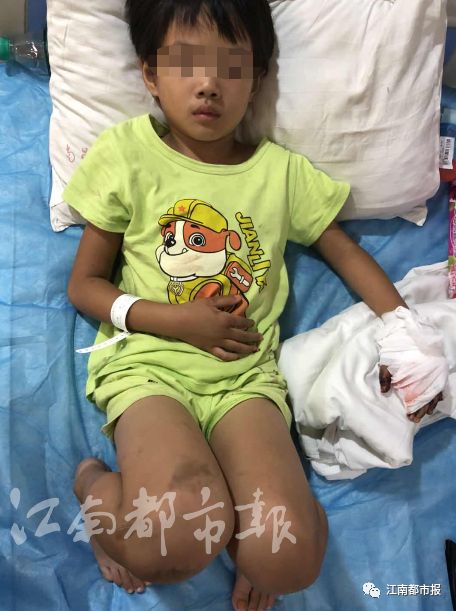

但孩子的手已严重变形

手术后,医生断定,贝贝左手中指和食指骨折,很难恢复,在成长过程中,手很容易长歪。目前,贝贝治疗已花费医药费2万元,后期还需1万元。